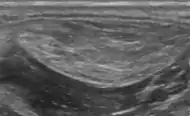

- Medical ultrasonography of a lipoma in the thenar eminence: It is hyperechoic compared to adjacent muscle, and relatively well-defined, with miniature hyperechoic lines.[23]